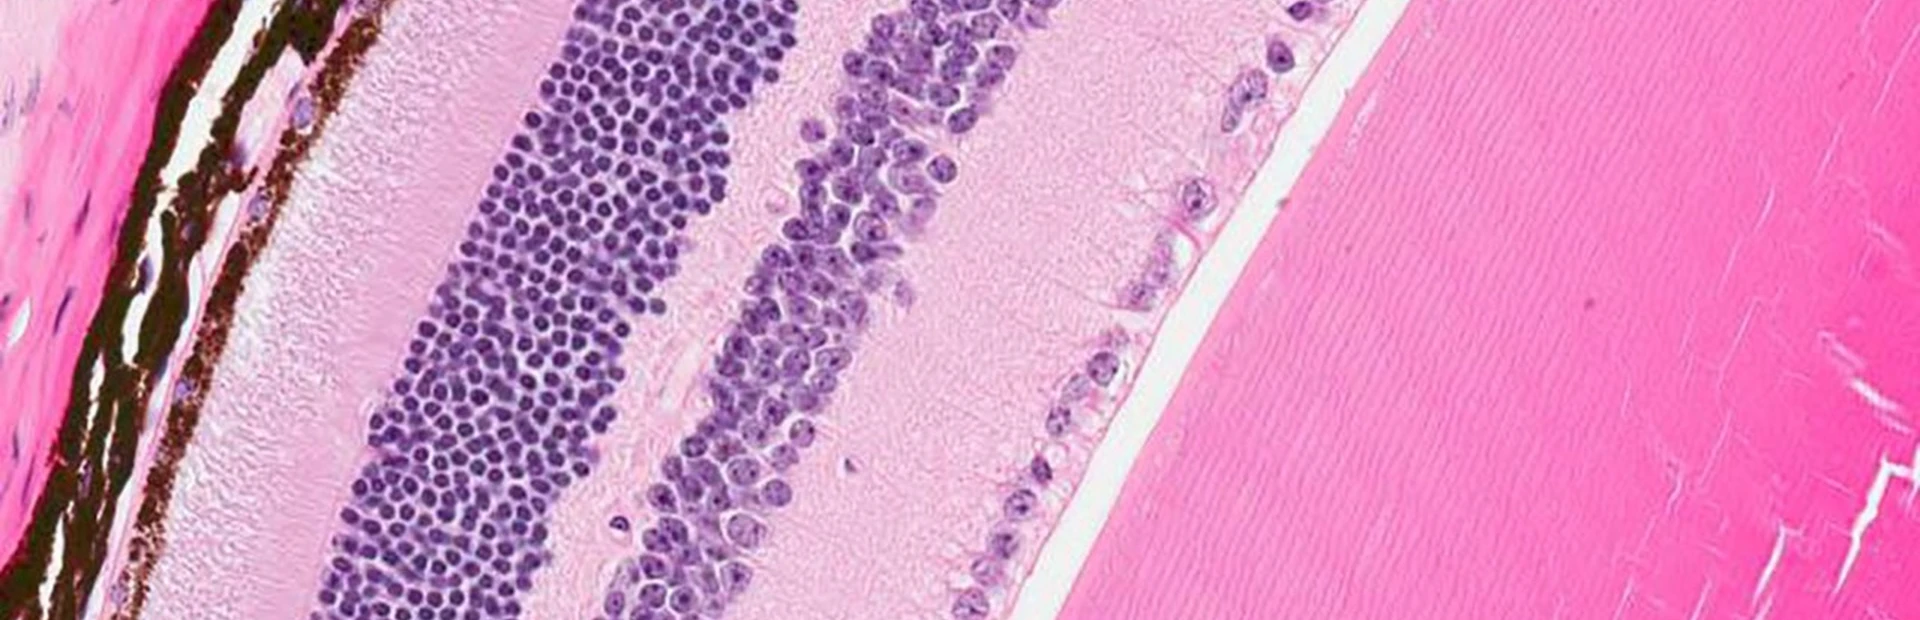

Morgan has retinitis pigmentosa (RP), which is a rare inherited disorder that cripples light-sensing cells in the retina (a layer of tissue in the back of the eye). Though it leads to visual problems in all patients, RP has varied genetic causes. In Morgan’s case, the culprit is a defective RLBP1 gene, which can’t make a crucial protein that light-sensing photoreceptor cells in the retina need to function properly. When deprived of that protein, the cells falter and eventually die, resulting in total blindness.

Main image: Novartis researchers designed a gene therapy aimed at repairing the protein-making machinery of diseased retina cells (some shown in brown) to potentially preserve visual function in patients with a rare disease. Image by Oliver Turner/Novartis